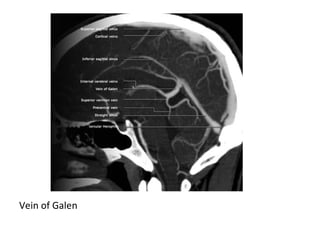

b) Deep Cerebral Veins :

-Consist of paired internal cerebral veins , the

basal vein of Rosenthal & the vein of Galen

-Lateral views of venous

phase circulation following

carotid artery injection

1 superior sagittal sinus

2 inferior sagittal sinus

4 transverse sinus

5 sigmoid sinus

6 jugular bulb

7 internal jugular vein

8 superficial cortical vein

10 vein of Labbé

11 superficial middle

cerebral vein

15 great cerebral vein of

Galen

16 basal vein of Rosenthal

24 straight sinus

1-Venous Occlusion :

Vein of Galen

Vein of Labbe (6) , Transverse sinus (3)

Vein of Trolard